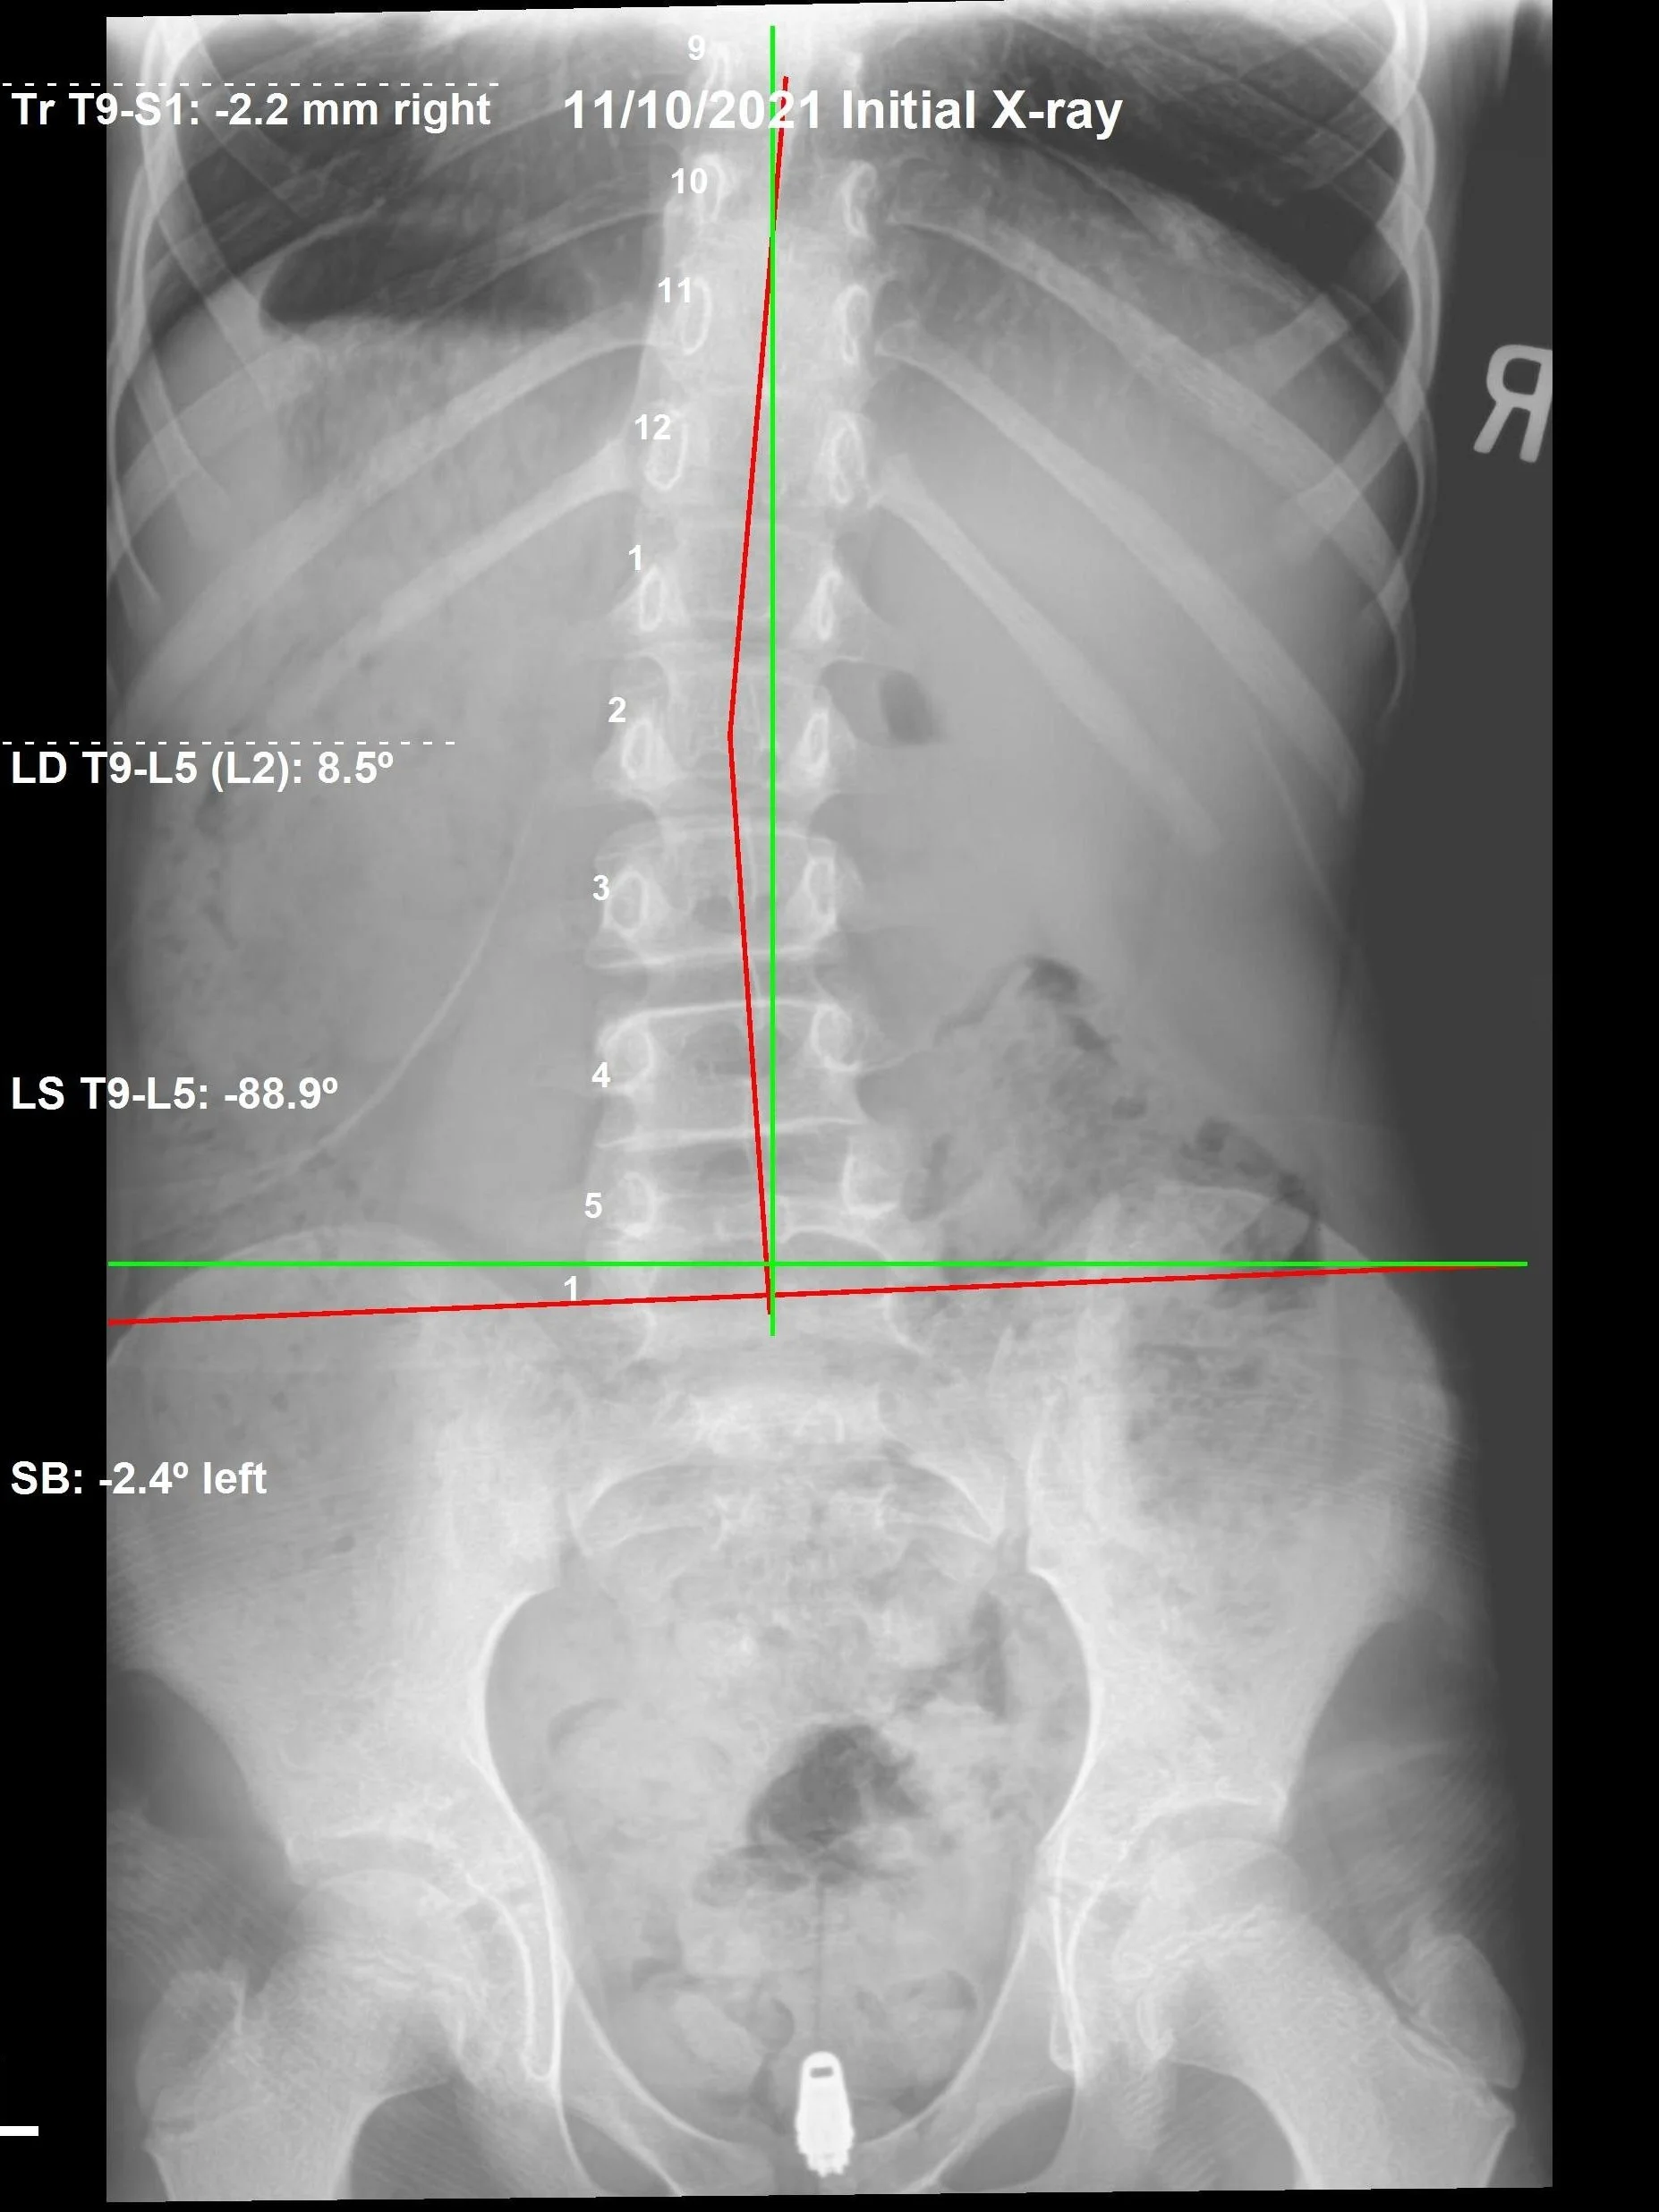

Correction of the Month